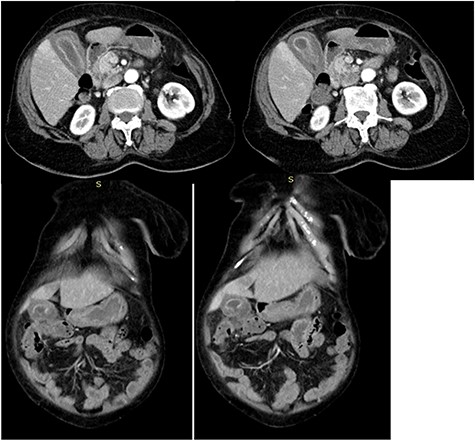

An 82-year-old female, with a history of hypertension for the past 10 years; and on amlodipine, presented to the emergency department (ED) complaining of sharp right upper quadrant pain for 1 day. The pain was of sudden onset, and progressively worsened, not associated with nausea or vomiting, or any changes in bowel habits. Her vital signs were: blood pressure of 144/89 mmHg, pulse rate of 66 beats/min, body temperature of 37 degrees Celsius; respiratory rate of 19 breaths/min and was saturating at 99% in room air. During physical examination, she was in agonizing pain, afebrile, not pale and not icteric. She had severe tenderness on the right hypochondriac region extending to the epigastric region, with Murphy’s sign positive and positive rebound tenderness indicating local peritonitis. At the ED, the patient was given tramadol to control the pain, and intravenous antibiotics were initiated. Chest X-ray, electrocardiography and other parameters were within normal range. Blood workup was done and showed a raised alanine aminotransferase of 50.30 U/L, (2.00–41.00). An abdominal ultrasound was performed, which showed a shrunken gallbladder with increased wall thickness-5 mm in size, and an impression of cholecystitis was made. A few hours post admission, the rebound tenderness was lost and hence an abdominal CT scan was ordered, for a confirmatory diagnosis. The abdominal CT scan reported diffuse thickening of the gallbladder with pericholecystic fluid collection. Perforation of the gallbladder was noted, with contained fluid collection around the transverse colon (hepatic flexure). No gallbladder calculus or mass was seen. Features were suggestive of perforated cholecystitis (Fig. 1). The patient was planned for an open cholecystectomy; the abdomen was then entered via a right Kocher’s incision. The gallbladder was identified and a concealed perforation was seen at the upper body, pulling the epiploic appendages of the transverse colon (Fig. 2). The appendages were released and a retrograde cholecystectomy was done. Hemostasis was achieved and the abdomen was closed in layers. Post-operative antibiotics and analgesics were given.

CT axial and coronal images of the abdomen showing diffuse thickening of the gall bladder with pericholecystic fluid collection; gallbladder perforation and fluid collection around the transverse colon (hepatic flexure) suggestive of contained perforated acalculuscholecytitis.